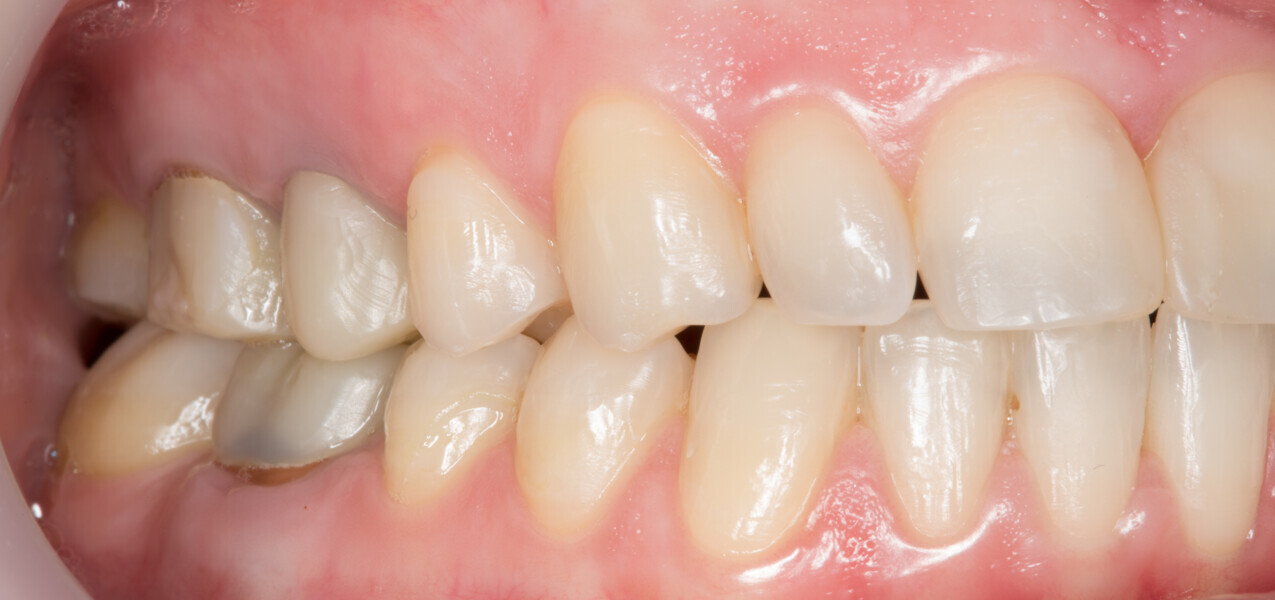

Fig. 16: Final analogue ceramic restorations.

Fig. 17: Final analogue ceramic restorations.

Fig. 18: Final analogue ceramic restorations.

Fig. 19: Final analogue ceramic restorations.